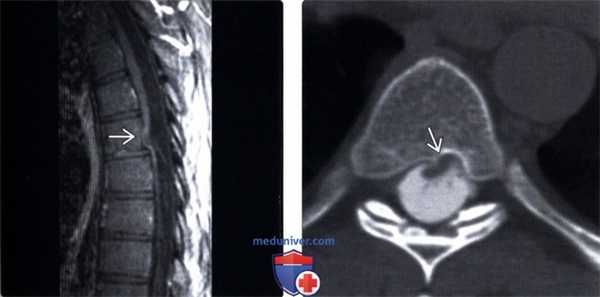

(Слева) Т1-ВИ, сагиттальная проекция: патогномоничная картина идиопатической трансдуральной грыжи верхнегрудного отдела спинного мозга с фокальной угловой его деформацией и вентральным смещением в дефект твердой мозговой оболочки.

(Справа) На аксиальной КТ-миелограмме типичная картина грыжи спинного мозга с вентральным его смещением до задней поверхности тела позвонка.